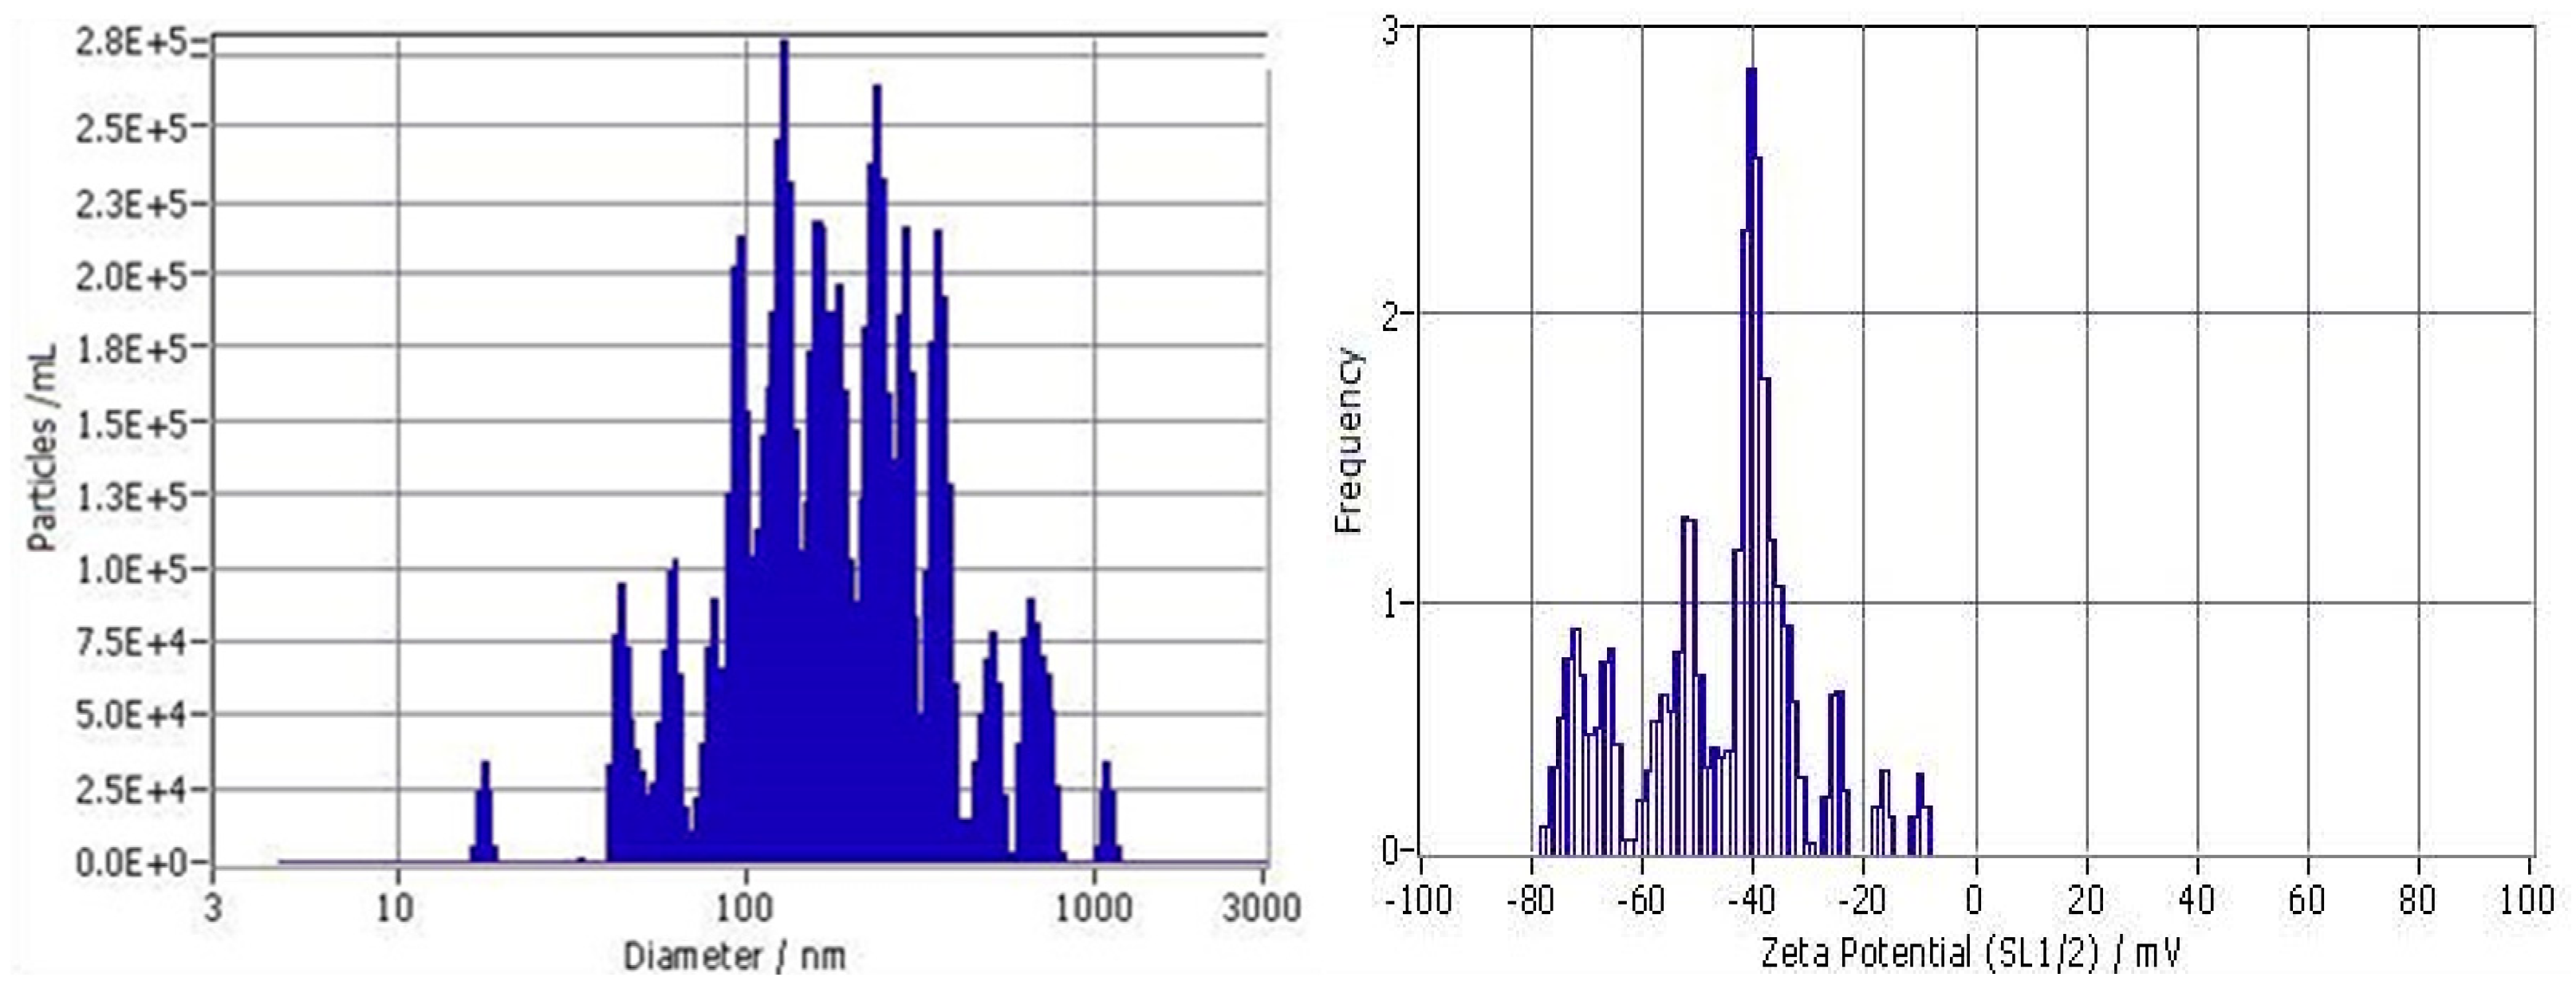

3.1. Size Distribution and Zeta Potential of Particles